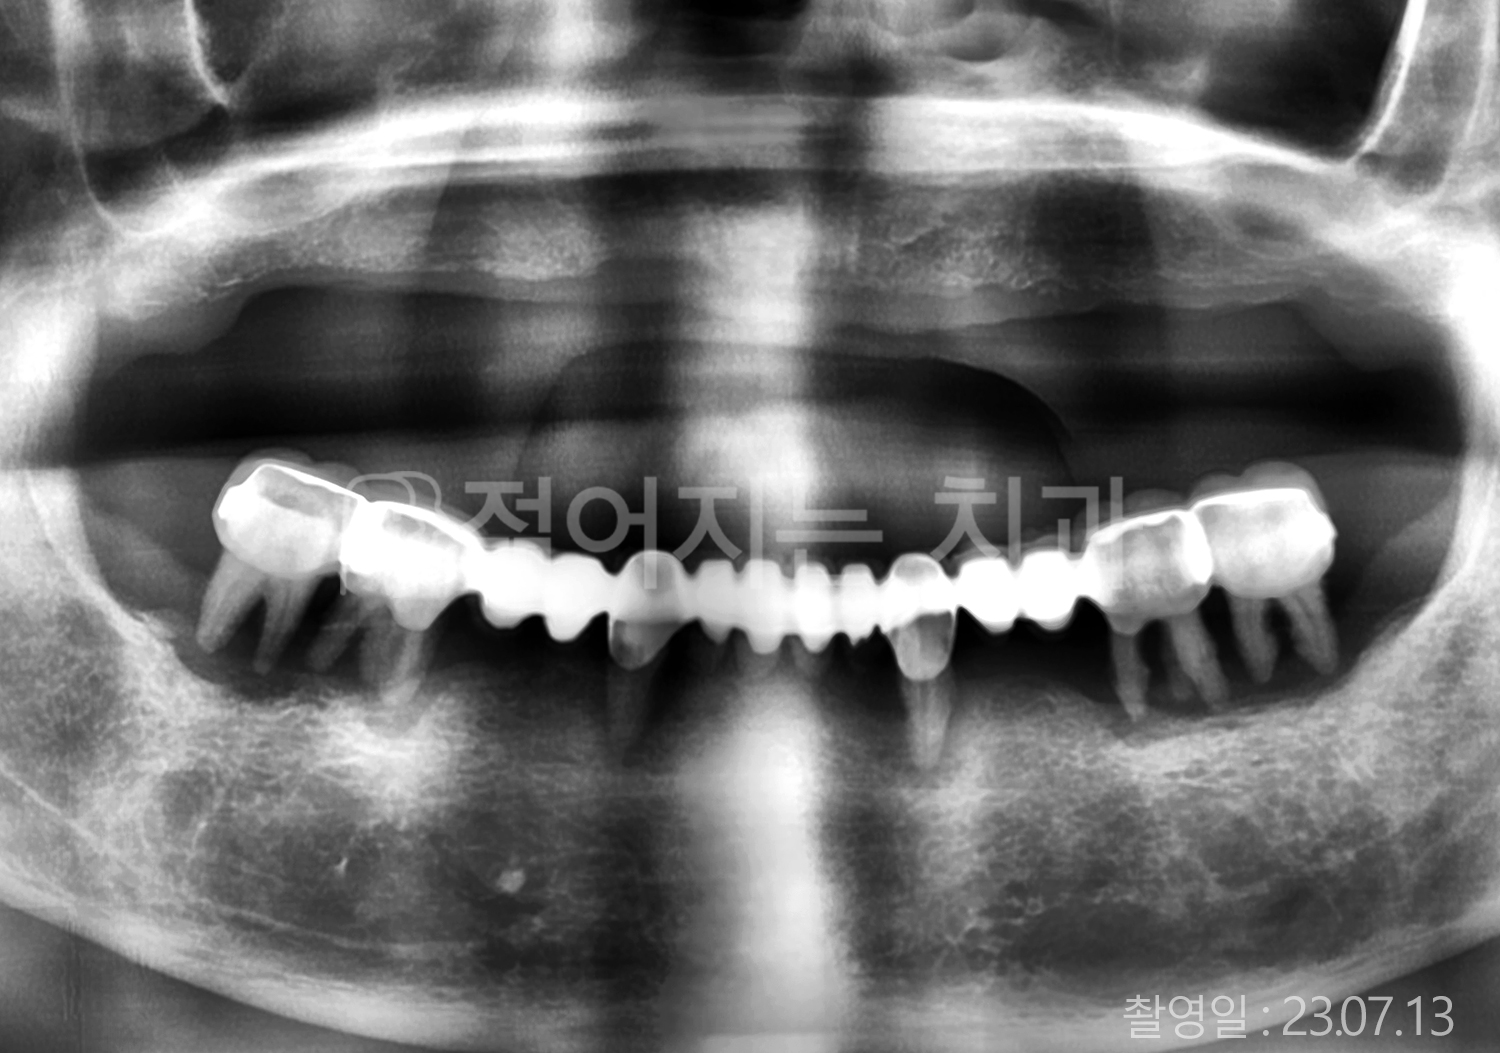

• 70대 고혈압, 당뇨 전체치아 10개 이상 임플란트

• 50대 고혈압, 당뇨 전체치아 10개 이상 임플란트

• 60대 고혈압, 당뇨 전체치아 10개 이상 임플란트

• 50대 전체치아 10개 이상 임플란트

• 70대 당뇨 전체치아 10개 이상 임플란트

• 80대 전체치아 10개 이상 임플란트

• 40대 전체치아 10개 이상 임플란트

• 60대 고협압, 고지혈증 전체치아 10개 이상 임플란트

• 60대 전체치아 10개 이상 임플란트

위 사진의 저작권은 젊어지는 치과에 있습니다.

* 위 사진은 동일 조건에서 촬영 되었습니다. / 모든 치료에는 부작용이 발생할 수 있습니다.